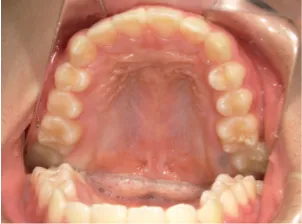

治療中④小2(8y2m)~小3(9y1m):QHとBHで拡大・アーチ形態の修正、ブラケットで前歯の並べ替えまで終了

| 行ったご提案・診断内容 | 成長期に行う治療と咬合治療をご提案 受け口用ファンクショナルアプライアンス(写真②③)からスタートし、小2以降で上下顎の拡大・歯列弓の形態修正・前歯の並べ直し(写真④)を行いその後、モノブロック(筋機能的咬合誘導)装置(写真⑤)へ移行し、受け口の再発予防と永久歯を適切な咬み合わせに誘導し、必要によりマルチブラケット法へ移行する治療方法を提案しました。 成長期治療(成長時期にお口の環境を整える治療) 2年生以降から 咬合治療 |

| 治療期間 | 12か月:受け口用ファンクショナルアプライアンス(写真②③) 12カ月:成長期治療の動的治療期間(写真④) 現在、成長の経過観察と咬合誘導中です(写真⑤~⑨) |